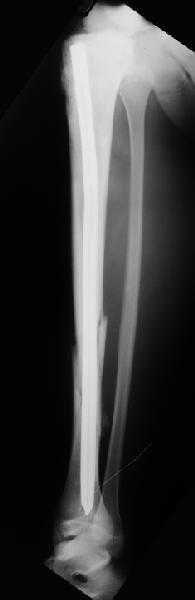

Вчера первый раз синтезировали голень гвоздем Fixion.

Спиральный оскольчатый перелом, ниже середины, у молодого парня. Сделали "классический" вариант гвоздя, который еще без винтов. Получилось все легко. Не торопясь, сделали операцию минут за 20. См. фото.

Дорогой Александр. Имею скромный опыт использования системы Fixion при переломах плеча, бедра и тибии. Всего 18 наблюдений с сентября 2006 г. Результаты отличные. Гвоздь индивидуален для каждого медуллярного канала. Легко имплантируется как в узкий, так и в деформированный канал. Это позволяет применять метод интрамедулярного остеосинтеза без ненужных потерь времени операции, флюороскопии и реально снижает крвопотерю и операционный риск. Удаление происходит без проблем. Особенно интересны больные с ипсилатеральными переломами бедра и голени.

В отношении ранней нагрузки при спиральных переломах лучше не торопиться. По данному случаю необходимо достигнуть исчезновения щели между штифтом и внутреним кортексом по Rg. А так картинка прекрасная - и длина сегмента и репозиция. Можно поздравить, коллега!

В Уфе начиная с апреля месяца 2007 года было установлено 35 интамедуллярных гвоздей Fixion. Из них без блокирования: 4 на плечо, 17 на голень, 8 на бедро, и 4 блокированных бедренных гвоздя.

Методика введения данных гвоздей оправдала себя с первых же попыток установления: минимальный разрез для доступа (3-4см), кровопотеря незначительная и естественно немаловажный фактор это время операции (в среднем 25 минут). Правда при выборе метода оперативного лечения нужно четко определять показания для установки этой системы